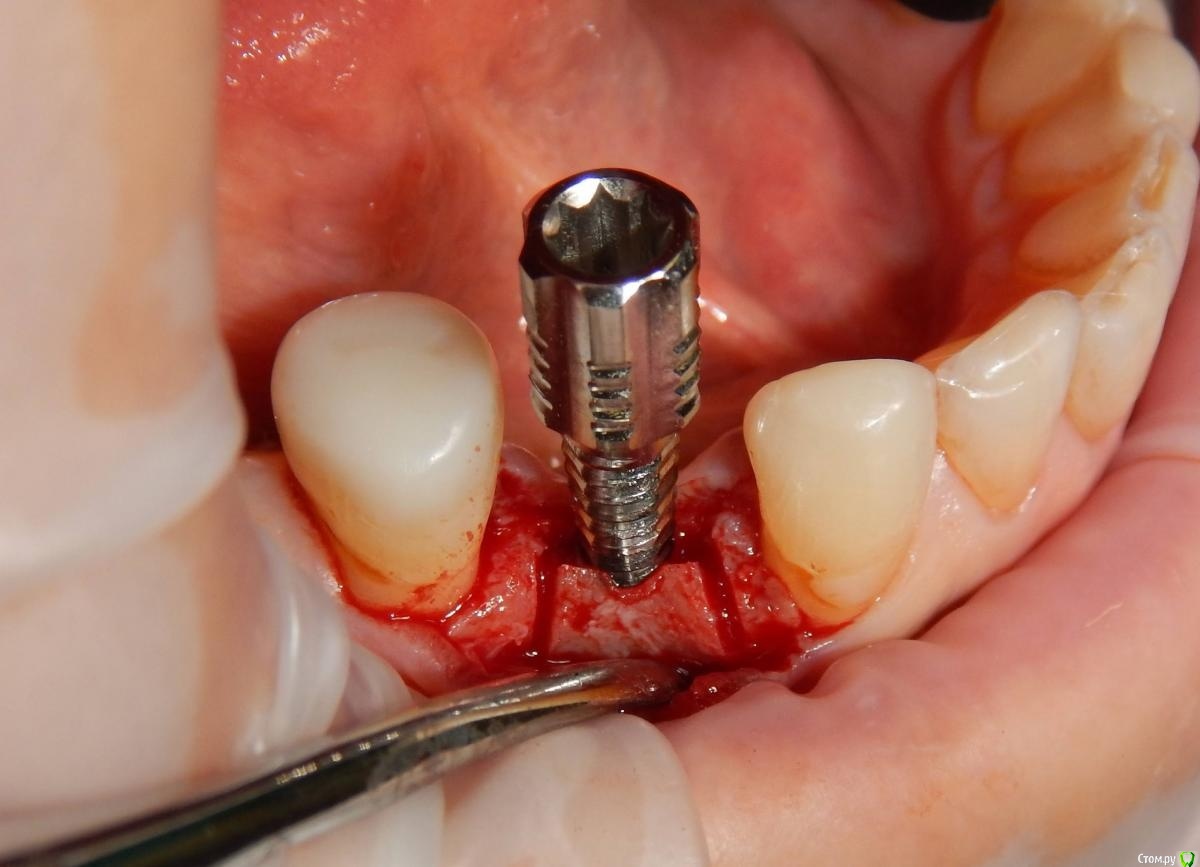

Astronaft Опубликовано 24 января, 2021 Поделиться Опубликовано 24 января, 2021 (изменено) Одиночный цирнокиевый имплантат и расщепление без графта. Пациентка:тонкая хрупкая женщина 55 лет, сконцентрированная на своем здоровье, в некоторой мере мнительная.всегда тяжелые заживления после удалений (по опросам)есть результаты Клиффорд теста (такая книжка под 200 страниц с in vitro аллерго-пробами на все известные материалы) Поставленная цель:только цирконий Мне было интересно найти вариант найболее приемленый пациентке и мне. С минимом хирургического риска и риском сожаления пациентки про выбор костного материала. Во-первых, я не использую аллографты - философски, чужие протеины, неприятный запах - просто основываясь на своем мнении.Во-вторых, мнительные пациенты склонны "пойти и почитать" до или потом и как следствие внушить себе вещи которых может и не было. Но по скольку мысль материальна... Все обсудил заранее.План: ридж сплит (расщепление), имплантат без графта, свободный СТ графт; если случается вестибулярная рецессия - пилим зирконий во рту. Ридж сплит сделан пьезотомом - крестальный и вертикальные пропилы на глубины около 8-10мм.Пилотное сверло.Развдвинул кость остеотомами от 1.6мм до 3.5мм в диаметре.Очень мягкая кость - напомнила мегкую максиллу плотности ногтевой пластинки вестибулярно.Имплант встал легко, но торк 40нсм. СТ графт из области 18. Деэпителизирую скальпелем уже потом. Тут интересно отметить, что я перестал боятся ошметков эпителия.Пончо сверху имплантата (а-ля шашлык Карлоса).Швы. PTFE всегда хорош. 12 недель.Красивая десна.Периотест -5.8 - отличный результат.Оттиск. Циркониевая коронка симметричная другой стороне. Изменено 24 января, 2021 пользователем Astronaft 19 Ссылка на комментарий

Astronaft Опубликовано 25 января, 2021 Автор Поделиться Опубликовано 25 января, 2021 Спасибо.День операции, 12 недель, день цементировки. 3 1 Ссылка на комментарий